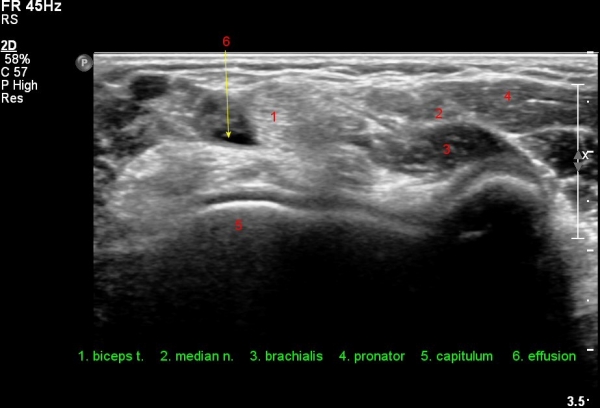

ÀÌµÎ¹Ú±Ù°Ç Á¾´Ü¸é°Ë»ç¿¡¼­ ¿ä°ñµ¹±âÀÇ µ¹Ãâ°ú °ñ±ØÀÌ °üÂûµÇ°í À̵θ·±Ù°ÇÀº Àú¿¡ÄÚ ºÎÁ¾°ú ¿¬°á ¼Ò½ÇÀÌ °üÂûµÊ(»çÁø 4, 5).